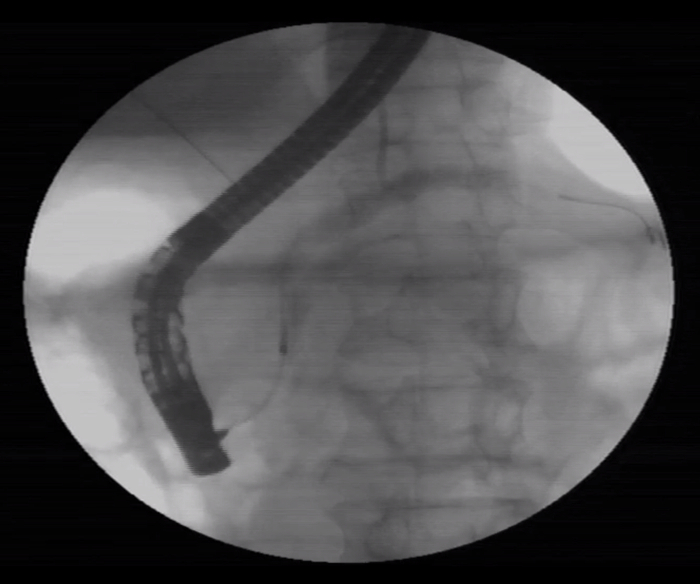

患者男,56岁,十二指肠镜提示慢性胰腺炎,CT下显示胰管结石。

CT下可见,结石狭窄处

导丝已插入胰管(右上